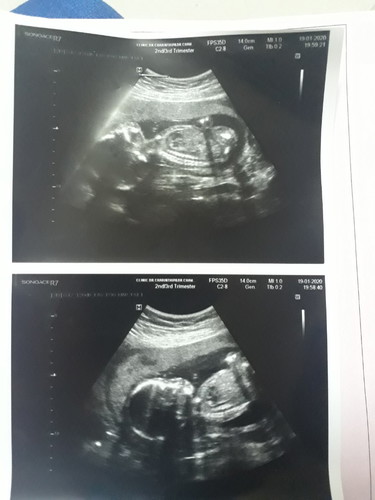

เมือวานหมอนัดอัลตราซาว์ดูเพศ หมอบอกว่าน้องเป็นผู้ชาย ดีใจมากสมใจที่อีพ่ออีแม่อยากได้ 18สัปดาห์